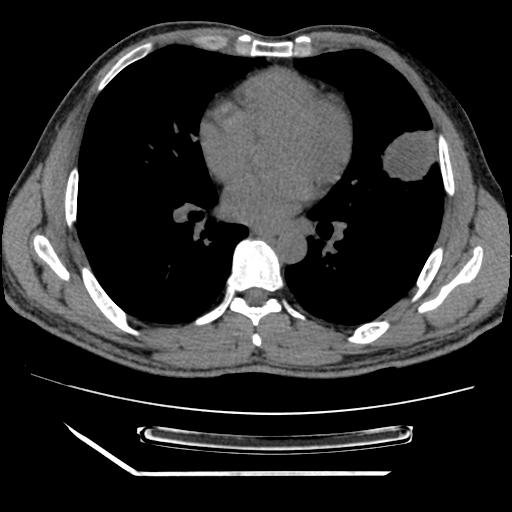

男,38岁,于2009年8月9日晚突发左侧胸痛,今x线提示左下肺阴影,为了明显确诊断,行ct检查,

血常规:嗜酸性细胞增高,单核细胞增高。

纵膈窗

病灶发生在下叶,密度均匀,边缘模糊、毛糙,周围血管纹理增强扭曲改变,靠近胸膜处病灶胸膜反应明显。

支持考虑---球形肺炎。

左肺舌叶病变。主体病灶呈类圆形中心密度低,成液化趋势周边班片影分布

考虑肺脓肿

虽然实验室检查支持炎性病变,且病变内有坏死改变(中央呈大片状低密度影),但仍不能掉以轻心,鳞癌也可以有这种影像改变。